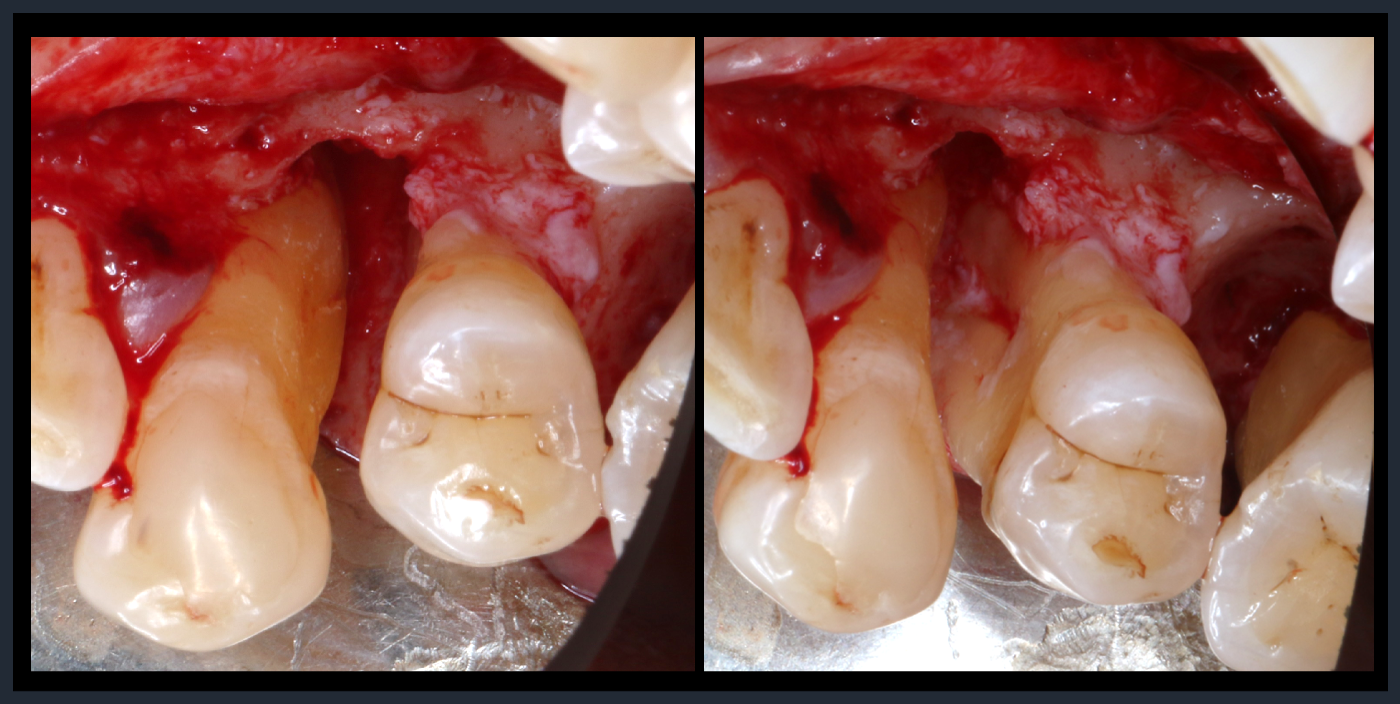

歯周組織再生療法

Periodontal tissue regeneration therapy

Periodontal tissue regeneration therapy

縁下歯石除去後。

歯周組織再生療法

Periodontal tissue regeneration therapy

Periodontal tissue regeneration therapy

縁下歯石除去後。

歯周組織再生療法

Periodontal tissue regeneration therapy

Periodontal tissue regeneration therapy

縁下歯石除去後。